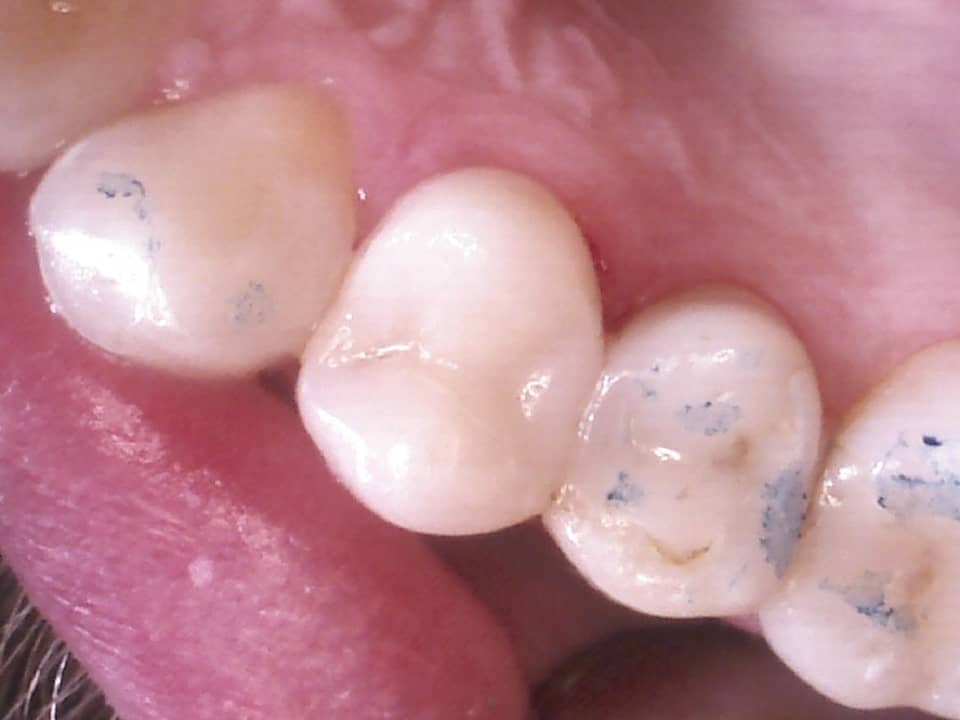

Sind Ihre Zähne doch einmal erkrankt – zum Beispiel an Karies – helfen wir Ihnen gerne, indem wir den Defekt mit Komposit- oder Amalgamfüllungen wieder reparieren.